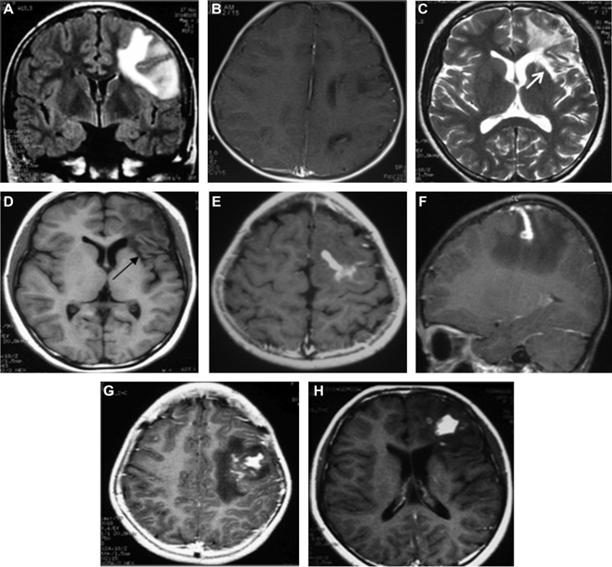

Bệnh ấu trùng sán nhái ở não (Cerebral sparganosis)

Thể bệnh này đặc trưng bởi các cơn động kinh cục bộ, lú lẫn, suy nhược, nhức đầu, giảm trí nhớ, hôn mê, sốt, dị cảm, yếu vận động, và một số triệu chứng khác ở thần kinh trung ương. Thể này thường liên quan đến một bán cầu não, đặc biệt thùy trán đỉnh (frontoparietal lobes), trong một số ca lan rộng đến tiểu não. Bệnh có thể gây nên xuất huyết não.

Nhiều nốt hình thành riêng rẽ dưới da có thể xuất hiện và biến mất theo thời gian. Các nốt thường ngứa, sưng phồng, đỏ lên và có di chuyển, thường kèm theo phù đau. Động kinh, co giật, dị cảm nửa thân mình và nhức đầu cũng là các triệu chứng thường gặp của bệnh sán nhái, đặc biệt bệnh sán nhái thể não và tăng bạch cầu ái toan cũng là dấu chứng cận lâm sàng hay thấy trên các ca như thế.

Hình 10-11. Một số thương tổn do sán nhái Spirometra spp. trên cơ quan thần kinh

Trong một trường hợp nhiễm trùng ở não do loài S. erinaceieuropaei, một người đàn ông đã điều trị nhức đầu, co giật, hồi tưởng trí nhớ và cảm giác có mùi lạ. Chụp cộng hưởng từ cho thấy một chùm các vòng tròn, lúc đầu ở bên thùy thái dương trung gian bên phải nhưng sau đó di chuyển theo thời gian đến các vùng khác của não. Nguyên nhân không được xác định trong vòng 4 năm cho đến khi phát hiện bệnh, cuối cùng sinh thiết mô đã cho thấy một con sán dài 1 cm tìm thấy và loại bỏ ra. Bệnh nhân tiếp tục chịu đựng các triệu chứng như vậy.

Hình 12. Ấu trùng sán nhái gây thương tổn nhiều vị trí khác nhau trên nhu mô não

Xác định vị trí thương tổn bằng chụp cắt lớp vi tính (CT) hoặc chụp cộng hưởng từ (MRI) sẽ giúp cho chẩn đoán bệnh sán nhái tốt, nhất là thể sán não. Rạch và loại bỏ thương tổn và xác định loài sán để đưa ra chẩn đoán xác định. Trong trường hợp thể não, xét nghiệm ELISA dịch não tủy hoặc xét nghiệm huyết thanh sẽ giúp ích nhiều cho chẩn đoán, nhưng thường được khẳng định sau khi đã bắt được con sán. Chụp CT giúp hỗ trợ cho chẩn đoán lâm sàng, thường thương tổn có đặc điểm giảm âm, dãn não thất, các nốt bất thường, có nhiều vùng can xi hóa. Các chuyên gia khuyên nên chụp lại CT để đánh giá sự thay đổi kích thước cũng như vị trí tổn thương để chỉ định điều trị kịp thời nếu vẫn còn thương tổn.

CT và MRI đặc biệt hiệu quả trong chẩn đoán bệnh sán nhái ở não vì các hình ảnh thể hiện trong nhu mô não. Thông qua phân tích hồi cứu 25 ca sán trên não từ năm 2000-2006, tác giả Song và cộng sự tìm thấy một số đặc điểm có thể áp dụng như một khung chẩn đoán áp dụng trong tương lai mà không cần thực hiện sinh thiết hay phẩu tích mô thương tổn. Đặc điểm tìm thấy phổ biến nhất là dấu đường hầm ("tunnel sign") trên phim MRI cho thấy vết di chuyển của sán, trong khi đó hình ảnh thường thấy là hình tăng đavòng tròn hợp nhất, hay nhiều hình tràng hạt (thường là 3-6 vòng). Siêu âm tổng quát với nhiều loại đầu dò khác nhau cũng cho thấy có hữu ích trong chẩn đoán nhiễm trùng sán nhái trên các mô mềm và một số tạng.

Các nghiên cứu của Song còn đề nghị bổ sung với các dữ liệu về bệnh sử lâm sàng, xét nghiệm ELISA và hình ảnh của MRI hay CT scans đủ để chẩn đoán bệnh sán nhái. Tuy nhiên, các thương tổn này đôi khi dễ bị nhầm lẫn với thương tổn do lao. Trong một trường hợp sán nhái ở não không được chẩn đoán trong vòng 4 năm, khi chụp đã cho thấy chùm vòng tròn do chuyển từ bên phải sang bên trái của não, cuối cùng sán đã được tìm thấy qua sinh thiết.